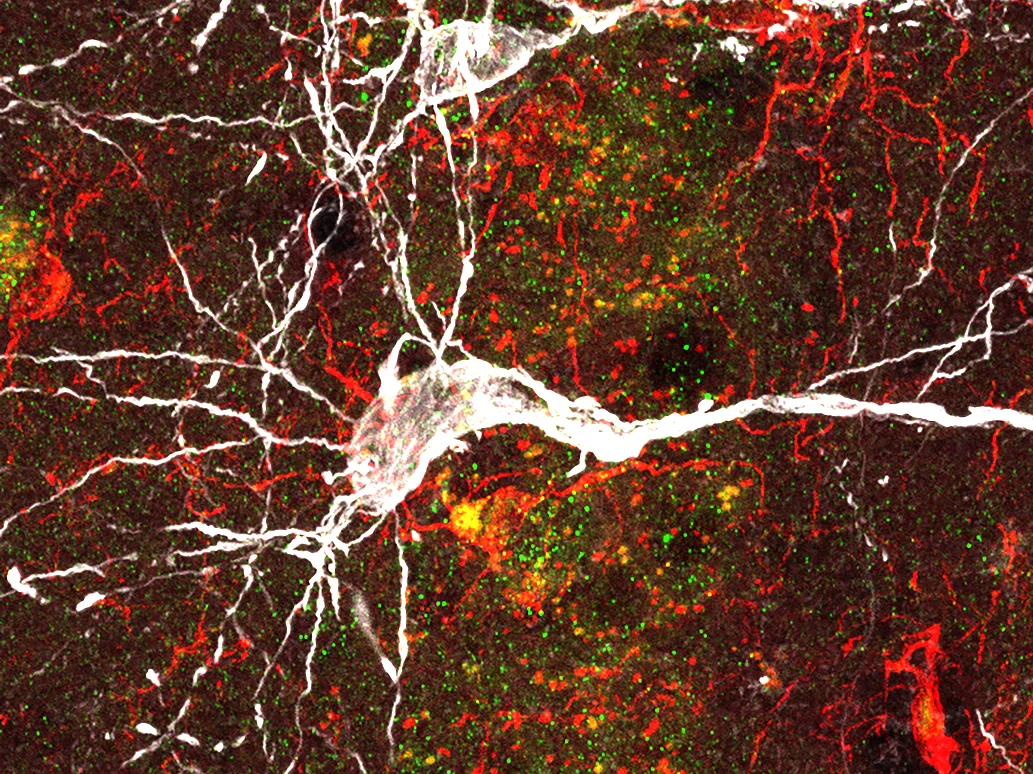

Nervenzelle (weiß) unter dem Mikroskop,

umgeben von Ablagerungen des sogenannten Amyloid-Beta-Proteins (rot). Diese Ablagerungen führen im Gehirn zu Entzündungen und treiben so die Alzheimer-Erkrankung voran.